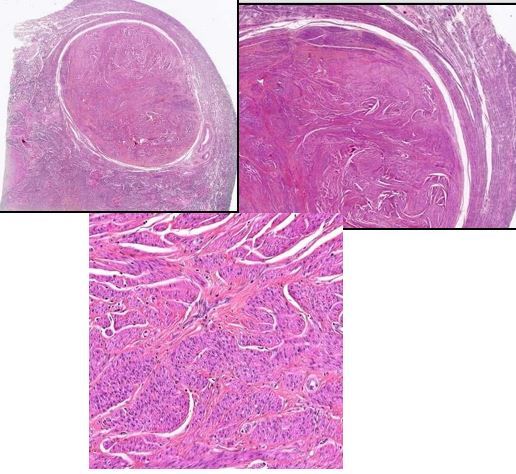

Léiomyome de l’utérus